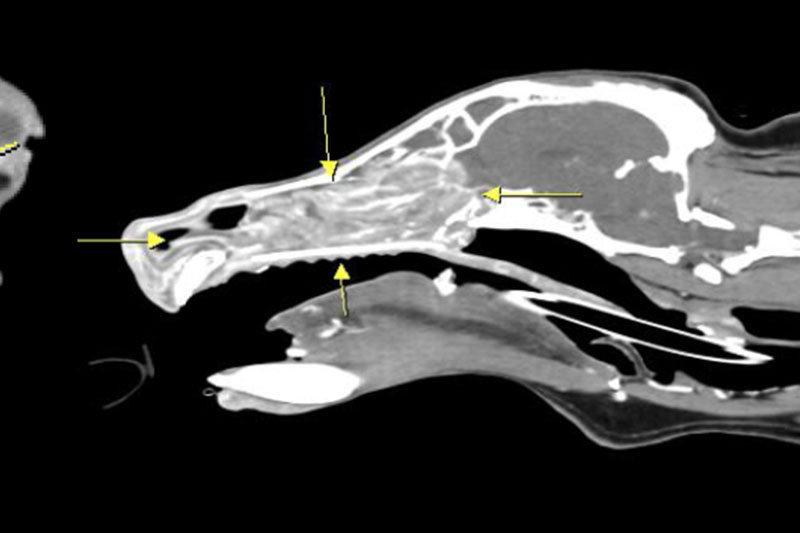

| 두부(머리) | 뇌종양, 두개골 골절, 중이염, 치주염, 안와(눈) 질환 등 |